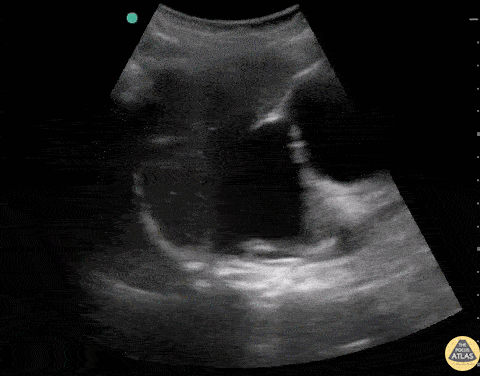

Renal/GU - Severe Hydronephrosis with Massive Hydroureter

Patient with urinary obstruction with severe hydronephrosis and absolutely massive hydroureter (CT confirmed). Dr. Stephen Alerhand - US Fellow - Mt Sinai Hospital, NYC